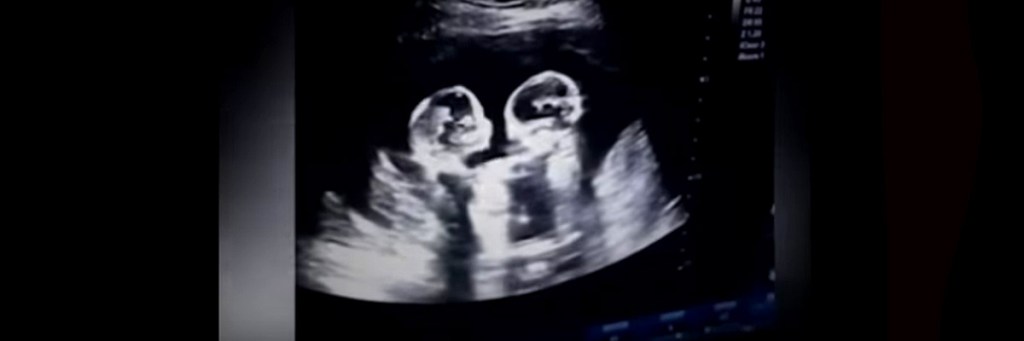

• Ultrasound of dangerous Mo-Mo pregnancy reveals two sisters fighting in the womb

Ultrasound of dangerous Mo-Mo pregnancy reveals two sisters fighting in the womb